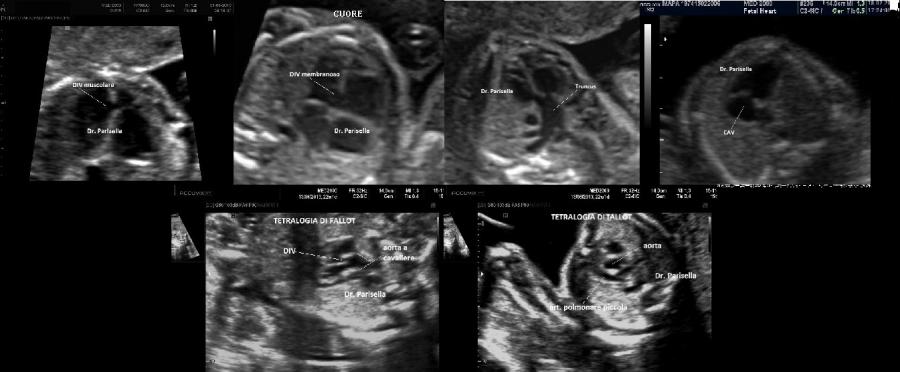

Possono essere presenti cardiopatie congenite come DIA, DIV, CAV, pervietà del dotto arterioso.